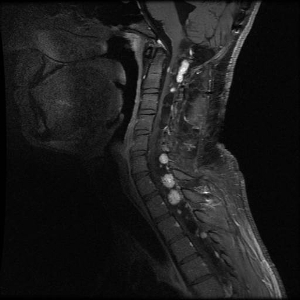

Hemangioblastomas are the most common disease manifestation in patients with VHL, affecting more than 70% of individuals. A prospective study assessed the natural history of hemangioblastomas.[16] The mean age at onset of central nervous system (CNS) hemangioblastomas is 29.1 years (range, 7–73 y).[17] CNS hemangioblastomas were most commonly seen in the cerebellum (45%), spinal cord (36%), cauda equina (11%), and brain stem (7%).[18] While sporadic hemangioblastomas are generally solitary in nature, the VHL-associated CNS lesions are often multifocal. After a mean follow-up of 7 years, 72% of the 225 patients studied developed new lesions.[18] Figures 2 and 3 depict cerebellar and spinal hemangioblastomas, respectively, in patients with VHL.

Sagittal view of an individual's neck showing several light-colored lesions along the spinal cord.

Figure 3. Hemangioblastomas are the most common disease manifestation in patients with von Hippel-Lindau disease. Multiple spinal cord hemangioblastomas are shown.